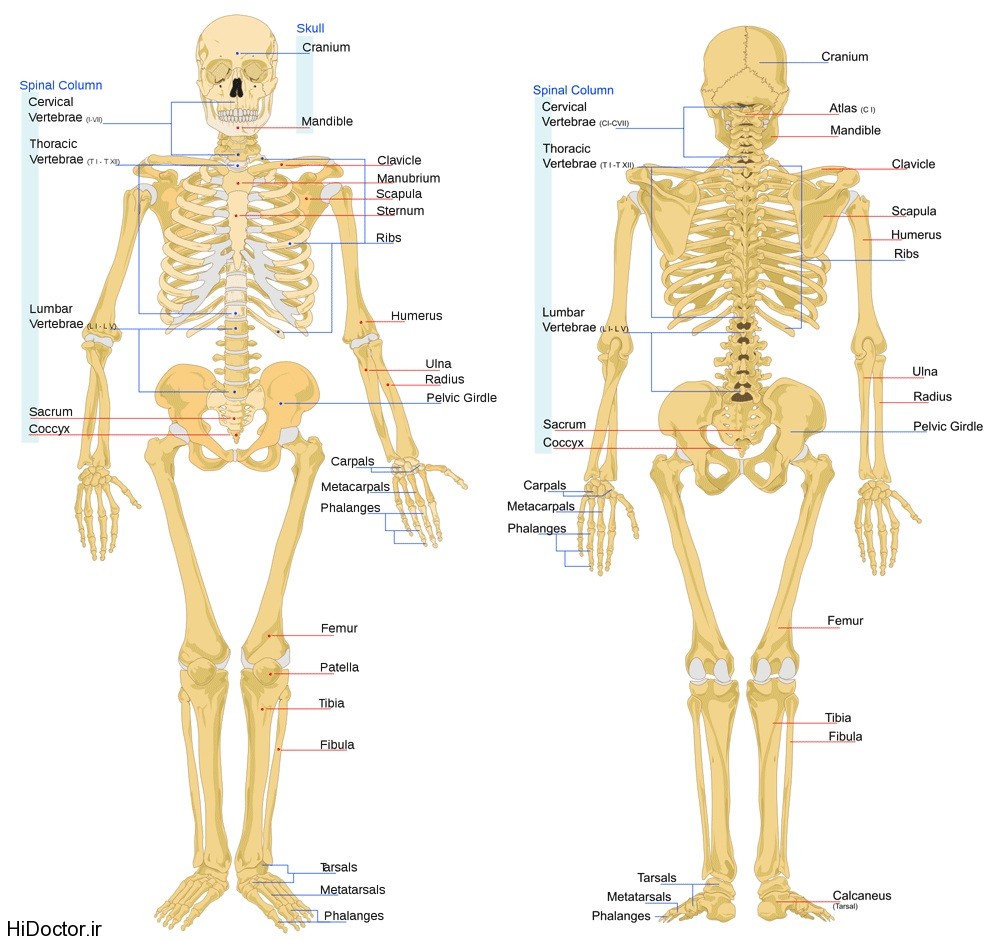

دانلود عکس اسکلت انسان دانلود عکس آناتومی بدن خانم از پشت و جلو دانلود عکس باکیفیت جمجمه انسان.

عکس اسکلت بدن انسان با کیفیت. عکس اسکلت عکس اسکلت برای پروفایل عکس اسکلت انسان عکس اسکلت خفن عکس اسکلت بدن انسان با کیفیت عکس اسکلت بدن انسان عکس اسکلت ترسناک عکس اسکلت فانتزی عکس اسکلت فانتزی دخترانه پرچم عکس اسکلت. عکس با کیفیت اسکلت داخلی انسان و درد و گرفتگی در ناحیه استخوان زانو ویژه استفاده در امور تبلیغاتی و تجاری طراحی کاتالوگ بروشور و تراکت با موضوع پزشکی فیزیوتراپی ارتوپد دکتر روماتیسم فیریوتراپ طب فیزیکی. عکس اسکلت بدن انسان زن و مرد آناتومی ساتین 16 سپتامبر 2017. اسکلت داربست بدن است تمام قسمت های بدن روی اسکلت قرارگرفته اند بدن انسان از ۲۰۶ قطعه استخوان تشکیل شده است این استخوان ها طوری با نظم کنار هم قرار گرفته اند که انسان را قادر می سازد حرکات دقیقی داشته باشد.

اسکلت جمجمه و گردن انسان ستون فقرات آناتومی اسکلت جمجمه و گردن انسان ستون فقرات آناتومی تصویر با کیفیت را از لینک زیر می توانید دانلود کنید. ۱ مطلب با کلمه ی کلیدی عکس اسکلت بدن انسان با کیفیت ثبت شده است گالری نسیم جدید ترین و با کیفیت ترین عکس های مناسبتی. عکس با کیفیت آناتومی اسکلت بدن انسان و درد و دیسک در قسمت مهره های ستون فقرات کمر ویژه استفاده در امور تبلیغاتی و تجاری طراحی کاتالوگ بروشور و تراکت با موضوع بیمارستان ها و کلینیک ها و درمانگاه ها و مطب ها پزشکان و.